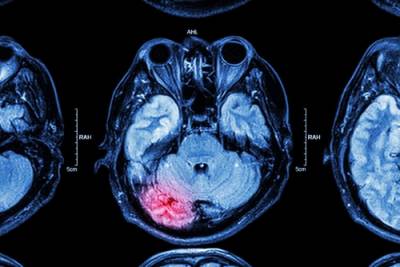

How Can Traumatic Brain Injuries Affect a Person’s Long-Term Health?

IL injury lawyerSerious injuries can occur in multiple different types of situations, ranging from car accidents to construction accidents or slip-and-fall accidents, and much more. While many injuries are evident at the time that an accident took place, others may not always be immediately obvious. Traumatic brain injuries (TBIs) often fall into the latter category, and the symptoms of these injuries may not become evident until days, weeks, or even months after the original incident. However, brain injuries can affect a person’s health and well-being for years, and in some cases, they can even lead to permanent impairment. Victims of these types of injuries should be sure to understand how they have been affected and how they can pursue compensation that will address the harm they have suffered.